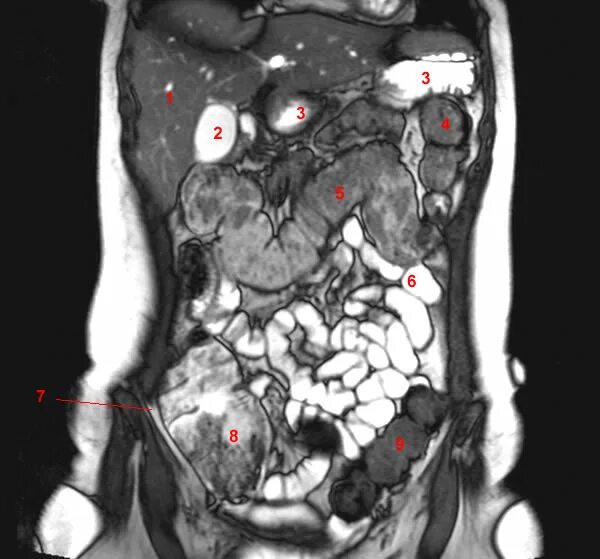

Рак брюшных лимфоузлов